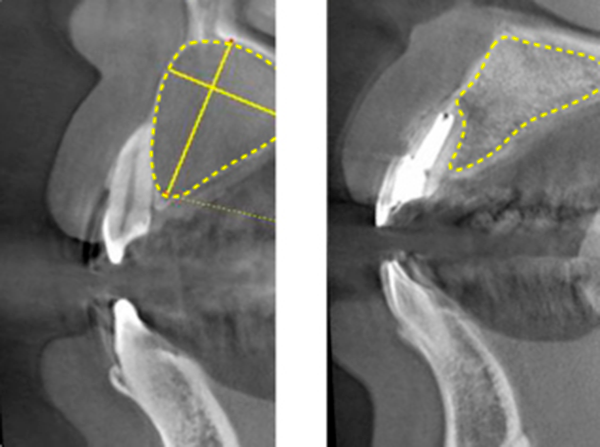

So, periapical lesion (where the bone around the root has dissolved) ever heal?

Does it just fall out?

No, they do not. Living organisms have a wonderful function called "immunity.

Even if the dentist is unable to clean it directly, about 60% of it will heal spontaneously.

In other words, by cleaning the inside of the root as well as possible, we block the source of nutrition for the bacteria around the root.

Then, immune response cells, which are the defense force, march in and attack the bacteria from the surrounding area.

If this defense force is able to eradicate the bacteria, the periapical lesion will heal.

(Figure 19)